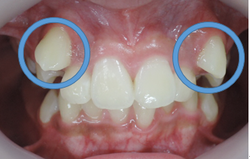

大人の矯正治療は出来るだけ見えにくい小さな矯正装置を利用して上の歯並びから歯ならび治していきます。埋伏している犬歯も萌出させていきます。

上顎の歯列がある程度改善してから下顎の歯列を見えにくいブラケットという矯正装置で整えていきます。埋伏している犬歯も萌出させていきます。

MEAW(マルチループ)により咬合高径(咬み合わせの高さ)を改善して美しい咬み合わせに治療していきます。(矯正開始から3カ月後)

終了時2か月前(1年3ヶ月後)

終了時(開始から1年8カ月後)

こどもの時から歯並びだけではなく上下顎骨に歪みがある症例です。

早期治療で上下顎骨や咬み合わせの高さを改善していたので素晴らしい歯並びになりました。

もしも早期治療をしないで大人になってから治療を開始したとすれば非抜歯での治療が困難となってしまう事もあるので早期治療をお勧めします。